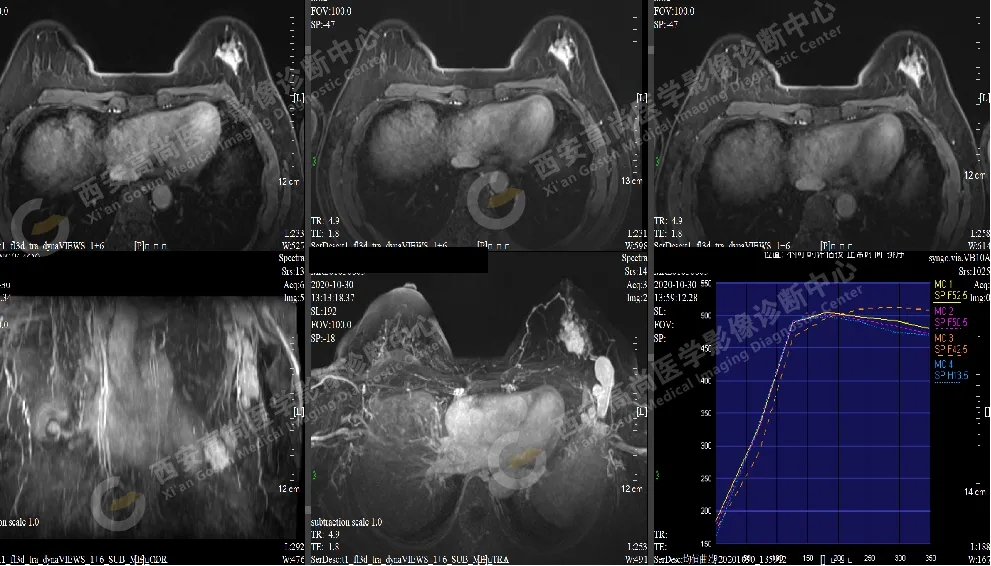

【病例一】女性,30歲,左側(cè)乳腺外下象限乳腺Ca(BI-RADS IV-V級(jí))